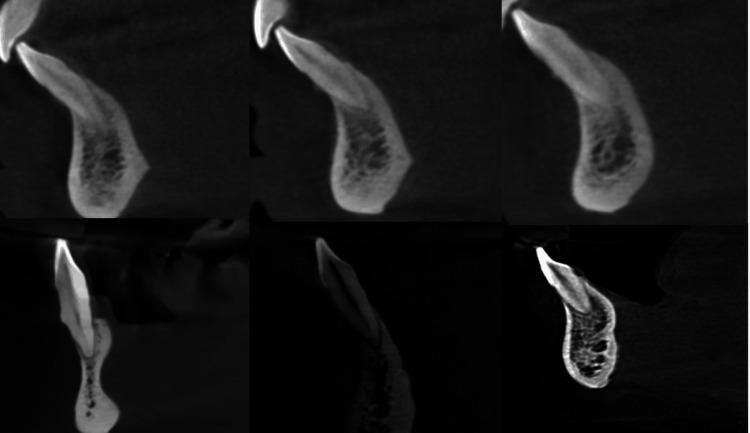

Aim Using two classifications, this study assessed root morphology and canal configuration and measured the Dentin thickness (DT) and canal shapes. Methods Cone beam computed tomography (CBCT) with 400 Mandibular Incisors was collected and assessed for the number, length, curvature of roots, number of canals, bifurcation level, configurations based on Vertucci's and Ahmed's classification, DT and canal shape at 3, 6, 9 mm from the apex. The collected data was subjected to statistical analysis with a level of significance at p<0.05. Results All samples had one root, averaging 12.769 ± 1.128 mm in central incisor (CI) and 13.044 ± 1.235 mm in lateral incisor (LI), with most roots being straight. Most samples had one canal in both teeth, with bifurcations most frequent in the middle third. The most frequent configuration was type 1 Vertucci or CI/LI by Ahmed, followed by type 3 or CI/LI. One sample, not classifiable under Vertucci, was classified as CI by Ahmed. The mean DT for CI was 3.18 ± 0.639 mm, 3.72 ± 0.671 mm and 4.43 ± 0.754 mm labiolingually and 1.578 ± 0.342 mm, 1.881 ± 0.374 mm, 2.283 ± 0.465 mm mesioditally at 3, 6, 9 mm from the apex, respectively. For LI, mean DT was 3.41 ± 0.916 mm, 3.90 ± 0.702 mm and 4.55 ± 0.746 mm labiolingually and 1.63 ± 0.322 mm, 1.981 ± 0.485 mm, 2.55 ± 0.470 mm mesioditally at 3, 6, 9 mm from the apex respectively, canal shape changed from oval to round, from apical to coronal. Conclusion Single canals were the most common, followed by two canals. The middle third of the canal had the most bifurcations. Vertucci type 1 or Ahmed's CI/LI  was the most commonly reported canal configuration, with one sample that could not be classified under Vertucci but could be classified using Ahmed classification. DT increased apical to coronal. The canal shape changed from oval to rounded, from apical to coronal.

目的 本研究使用两种分类方法评估牙根形态和根管形态,并测量牙本质厚度(DT)和根管形状。方法 收集400颗下颌切牙的锥形束计算机断层扫描(CBCT)图像,评估牙根的数量、长度、弯曲度、根管数量、分叉水平,根据Vertucci分类法和Ahmed分类法评估根管形态,测量根尖3、6、9 mm处的DT和根管形状。对收集的数据进行统计学分析,显著性水平为p<0.05。结果 所有样本均有一个牙根,中切牙(CI)平均长度为12.769±1.128 mm,侧切牙(LI)平均长度为13.044±1.235 mm,大多数牙根为直根。大多数样本的两颗牙均有一个根管,分叉最常见于中1/3处。最常见的形态为Vertucci分类法中的1型或Ahmed分类法中的CI/LI,其次是3型或CI/LI。有一个样本无法按照Vertucci分类法分类,但按照Ahmed分类法可归为CI。CI在根尖3、6、9 mm处的唇舌向平均DT分别为3.18±0.639 mm、3.72±0.671 mm和4.43±0.754 mm,近远中向平均DT分别为1.578±0.342 mm、1.881±0.374 mm和2.283±0.465 mm。LI在根尖3、6、9 mm处的唇舌向平均DT分别为3.41±0.916 mm、3.90±0.702 mm和4.55±0.746 mm,近远中向平均DT分别为1.63±0.322 mm、1.981±0.485 mm和2.55±0.470 mm,根管形状从根尖向冠方由椭圆形变为圆形。结论 单根管最为常见,其次是双根管。根管的中1/3处分叉最多。Vertucci 1型或Ahmed的CI/LI是最常报道的根管形态,有一个样本无法按照Vertucci分类法分类,但可按照Ahmed分类法分类。DT从根尖向冠方增加。根管形状从根尖向冠方由椭圆形变为圆形。